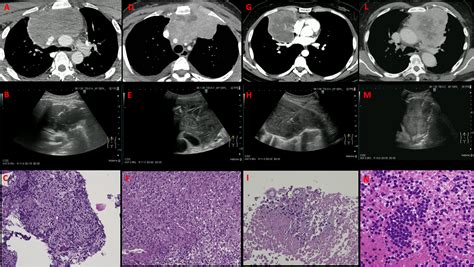

Diagnostic Approaches and Imaging

When a patient presents with symptoms such as persistent cough, chest pain, or difficulty breathing, medical professionals will initiate a diagnostic journey to confirm the presence of a Mass Anterior Mediastinum. Initial physical examinations are often followed by advanced imaging techniques, which are crucial for mapping the size, shape, and relationship of the mass to vital structures.

CT Scan (Contrast-enhanced) The gold standard for determining the exact location and extent of the mass.